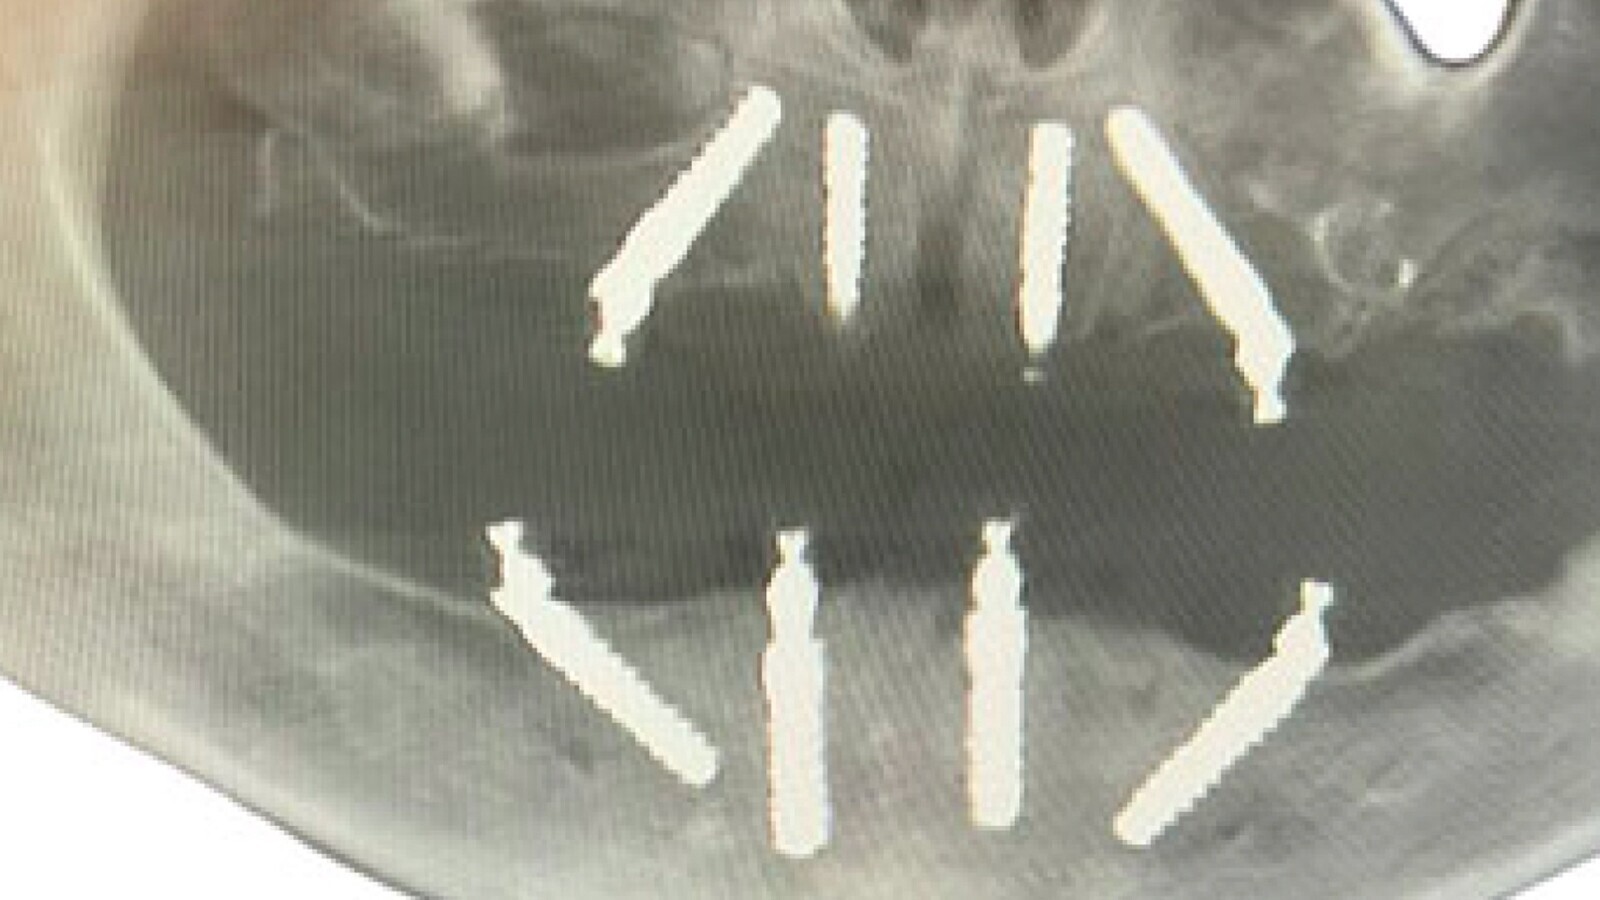

Figura 7. Radiografía de la colocación de los implantes realizada con cirugía guiada.